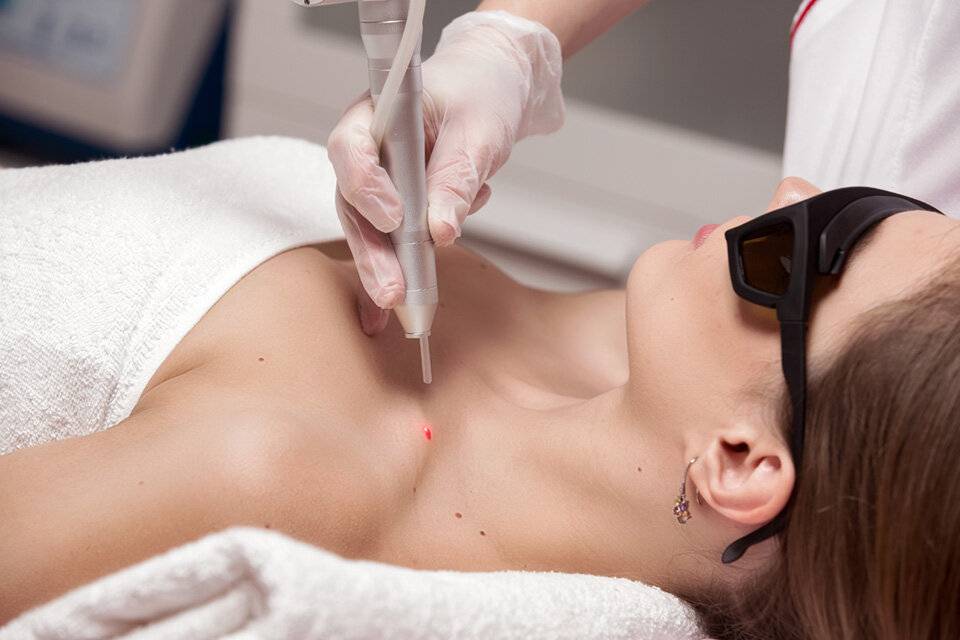

Лазерная терапия

Фото: лазерное удаление

В его основе лежит воздействие лазерным лучом на тело папилломы. При помощи сверхкоротких последовательных волновых импульсов и происходит очищение кожи. Здоровый участок при этом не повреждается.

Как правило, клиника, где удаляют лазером бородавки, имеет соответствующие лицензии и сертификаты, и вы можете быть уверены в качестве услуг.

- Лазерное удаление широко применяется для удаления бородавок на лице, подмышками, а также в интимных местах.

Процедура признается высокоэффективной и безболезненной.